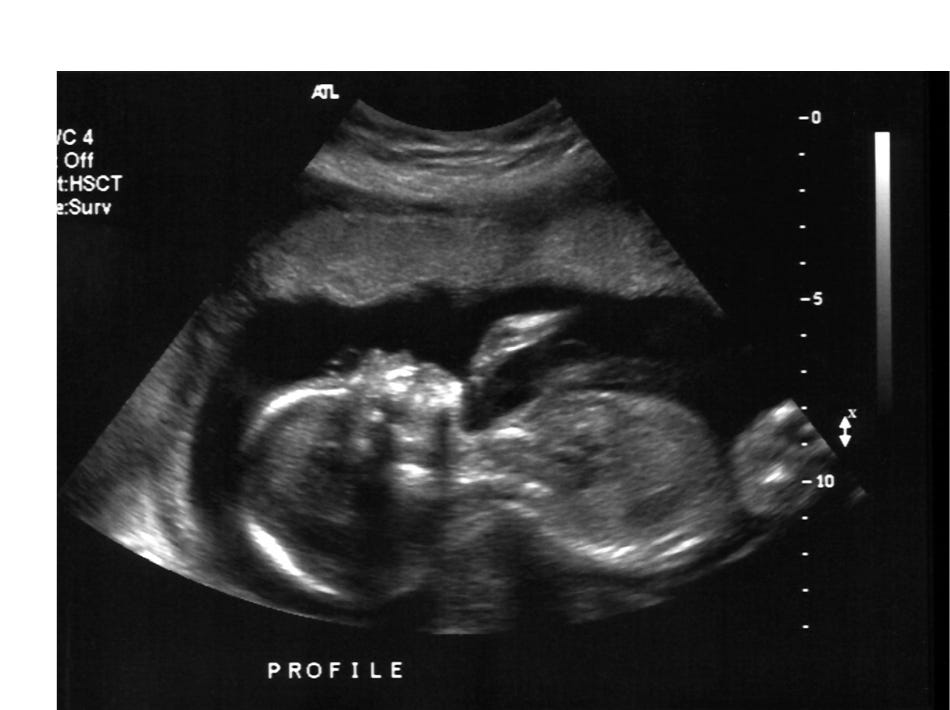

Here is an ultrasound of a 16-week-old preborn baby. This would be the 18th week of pregnancy, within the time frame.

I saw a head with a brain. I saw little arms followed by 10 little fingers. I saw tiny legs with two tiny feet moving and kicking around.

But most of all, I saw and heard a beating heart. I lay there watching my daughter’s steady beating heart, and I knew that baby was my baby.